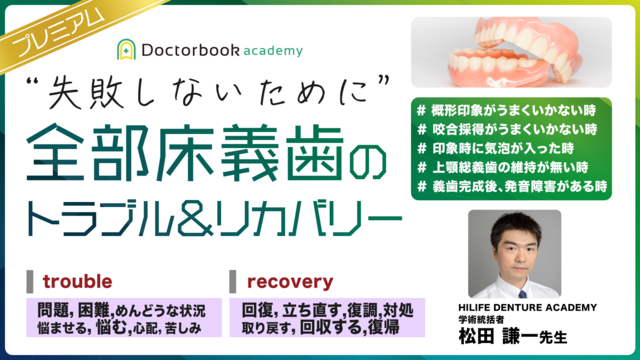

あくまで「中古」とご理解のうえご入札をお願いします。失敗しないために” 全部床義歯のトラブル&リカバリー。